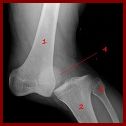

Fracture :

Pas toujours évident à repérer sur le terrain et à différencier d’une entorse, au moindre doute partez du principe que c’est cassé. Les signes qui doivent faire évoquer la fracture sont la notion de craquement, de déformation d’un membre, l’impossibilité de bouger le membre, de le mettre en appui et l’existence d’une douleur localisée.

Prise en charge :

– NB : Toute notion de craquement lors de l’accident, tout gonflement extreme ou douleur anormalement forte doit vous amener à consulter un médecin pour éliminer une fracture.